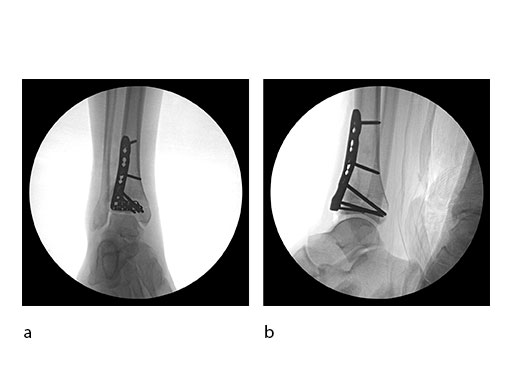

Surgeons performed an anterolateral surgical approach and distracted the joint using the distraction clamp and osteotome (Fig 2). The fracture was fixated with a VA-LCP Anterolateral Distal Tibia Plate (Fig 35).